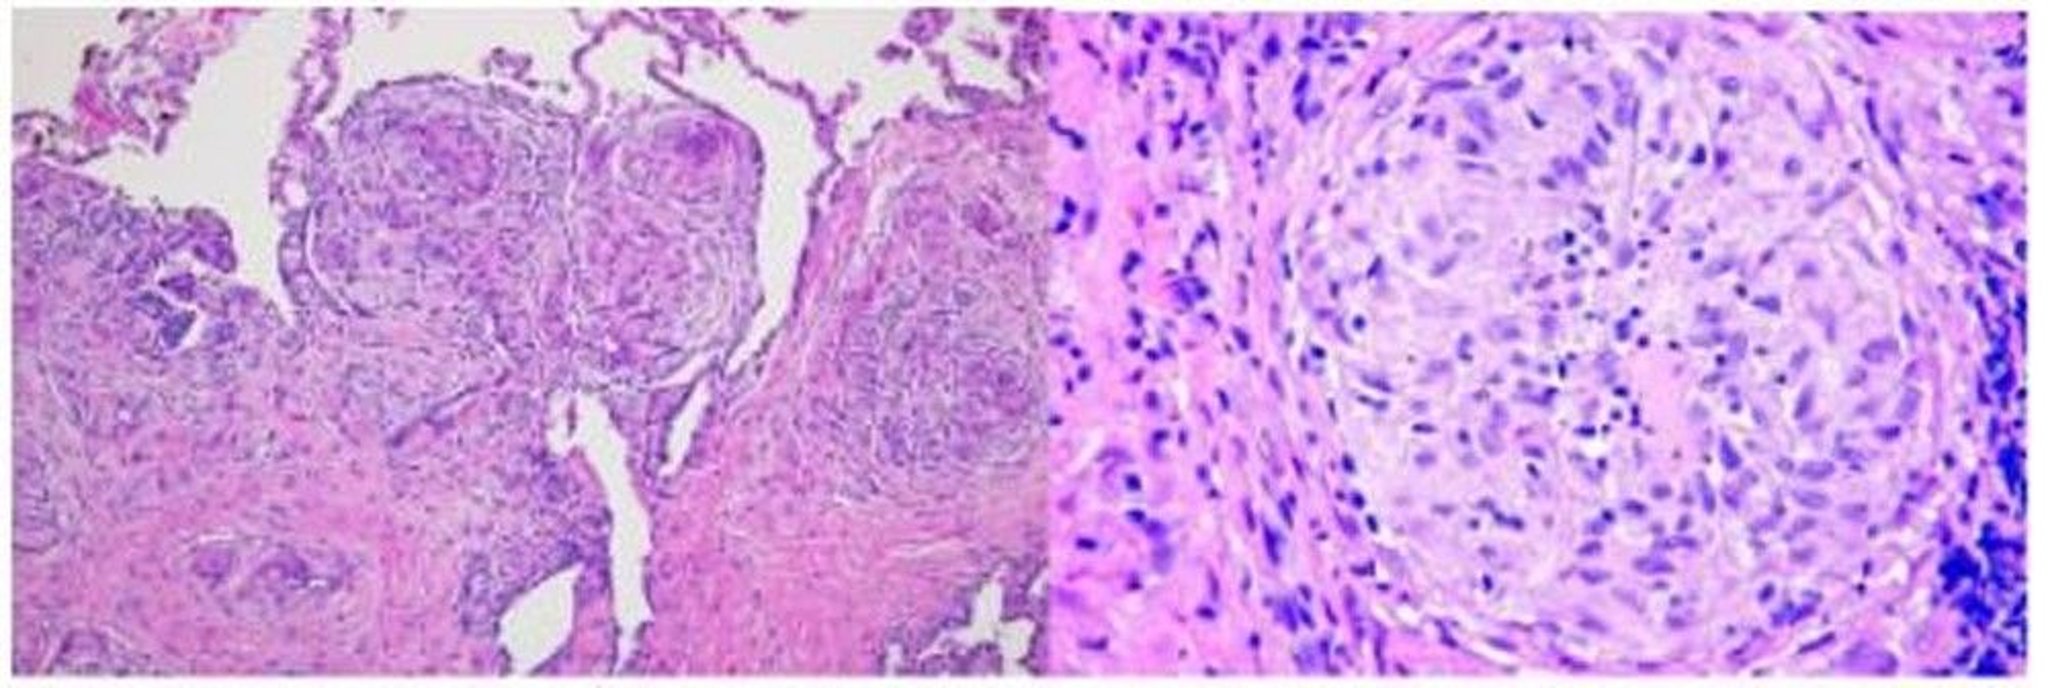

Sarkoidose (Histopathologie)

In diesem Bild zeigt eine Lungenbiopsie eines Patienten mit Sarkoidose Granulome entlang des bronchovaskulären Bündels (Hämatoxylin- und Eosinfärbung, geringe Vergrößerung; links) und Sarkoidgranulome mit vielkernigen Riesenzellen in der Mitte der Granulome (hohe Vergrößerung; rechts).

Image courtesy of Birendra P. Sah, MD, FCCP.